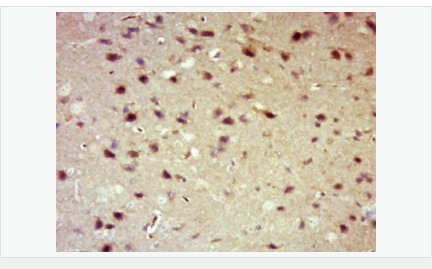

| 產(chǎn)品應(yīng)用 | WB=1:500-2000 IHC-P=1:100-500 IHC-F=1:100-500 Flow-Cyt=1μg /test. IF=1:100-500 (石蠟切片需做抗原修復(fù)) not yet tested in other applications. optimal dilutions/concentrations should be determined by the end user. |

| 產(chǎn)品介紹 | 14-3-3 are activates tyrosine and tryptophan hydroxylases in the presence of Ca (2+)/calmodulin-dependent protein kinase II, and strongly activates protein kinase C. Is probably a multifunctional regulator of the cell signaling processes mediated by both kinases. Activates the ADP-ribosyltransferase (exoS) activity of bacterial origin. 14-3-3 proteins are localized in neurons, and are axonally transported to the nerve terminals. They may be also present, at lower levels, in various other eukaryotic tissues. It belongs to the 14-3-3 family. This antibody is reactive with 14-3-3 Alpha, Beta, Gamma, Delta, Epsilon. Function: Adapter protein implicated in the regulation of a large spectrum of both general and specialized signaling pathways. Binds to a large number of partners, usually by recognition of a phosphoserine or phosphothreonine motif. Binding generally results in the modulation of the activity of the binding partner. Subunit: Interacts with CDK16 and BSPRY. Interacts with WEE1 (C-terminal). Interacts with SAMSN1. Interacts with MLF1 (phosphorylated form); the interaction retains it in the cytoplasm. Interacts with Thr-phosphorylated ITGB2. Interacts with BCL2L11. Homodimer. Heterodimerizes with YWHAE. Homo- and hetero-dimerization is inhibited by phosphorylation on Ser-58. Interacts with FOXO4, NOXA1, SSH1 and ARHGEF2. Interacts with Pseudomonas aeruginosa exoS (unphosphorylated form). Interacts with BAX; the interaction occurs in the cytoplasm. Under stress conditions, MAPK8-mediated phosphorylation releases BAX to mitochondria. Interacts with phosphorylated RAF1; the interaction is inhibited when YWHAZ is phosphorylated on Thr-232. Interacts with TP53; the interaction enhances p53 transcriptional activity. The Ser-58 phosphorylated form inhibits this interaction and p53 transcriptional activity. Interacts with ABL1 (phosphorylated form); the interaction retains ABL1 in the cytoplasm. Interacts with PKA-phosphorylated AANAT; the interaction modulates AANAT enzymatic activity by increasing affinity for arylalkylamines and acetyl-CoA and protecting the enzyme from dephosphorylation and proteasomal degradation. It may also prevent thiol-dependent inactivation. Interacts with AKT1; the interaction phosphorylates YWHAZ and modulates dimerization. Interacts with GAB2 and TLK2. Subcellular Location: Cytoplasm. Melanosome. Note=Located to stage I to stage IV melanosomes. Post-translational modifications: The delta, brain-specific form differs from the zeta form in being phosphorylated. Phosphorylation on Ser-184 by MAPK8; promotes dissociation of BAX and translocation of BAX to mitochondria. Phosphorylation on Ser-58 by PKA; disrupts homodimerization and heterodimerization with YHAE and TP53. This phosphorylation appears to be activated by sphingosine. Phosphorylation on Thr-232; inhibits binding of RAF1. Similarity: Belongs to the 14-3-3 family. SWISS: P31946 Gene ID: 7529 Database links: Entrez Gene: 7529 Human Entrez Gene: 54401 Mouse Omim: 601289 Human SwissProt: P31946 Human SwissProt: Q9CQV8 Mouse Unigene: 643544 Human Unigene: 34319 Mouse Unigene: 485025 Mouse Unigene: 8653 Rat Important Note: This product as supplied is intended for research use only, not for use in human, therapeutic or diagnostic applications. 信號傳導(dǎo)(Signaling Intermediates) 14-3-3蛋白是一個(gè)涉及調(diào)節(jié)細(xì)胞凋亡、促細(xì)胞分裂信號傳導(dǎo)和細(xì)胞周期關(guān)卡的蛋白質(zhì)家族。它被認(rèn)為是通過與絲氨酸殘基磷酸化的蛋白質(zhì)的結(jié)合介導(dǎo)的信號傳導(dǎo)中的關(guān)鍵調(diào)節(jié)物。通過與Bad(相關(guān)死亡因子)的結(jié)合, 14-3-3 蛋白由于將Bad隔離于胞液而防止了細(xì)胞凋亡。 蛋白是14-3-3家族成員。它廣泛分布于哺乳動物、兩棲類、昆蟲、植物和酵母菌的真核生物高度保守性多功能蛋白質(zhì)。 目前已知至少有16個(gè)成員。此抗體識別分子量為30-31kDa的14-3-3蛋白αβγδε亞型。 |